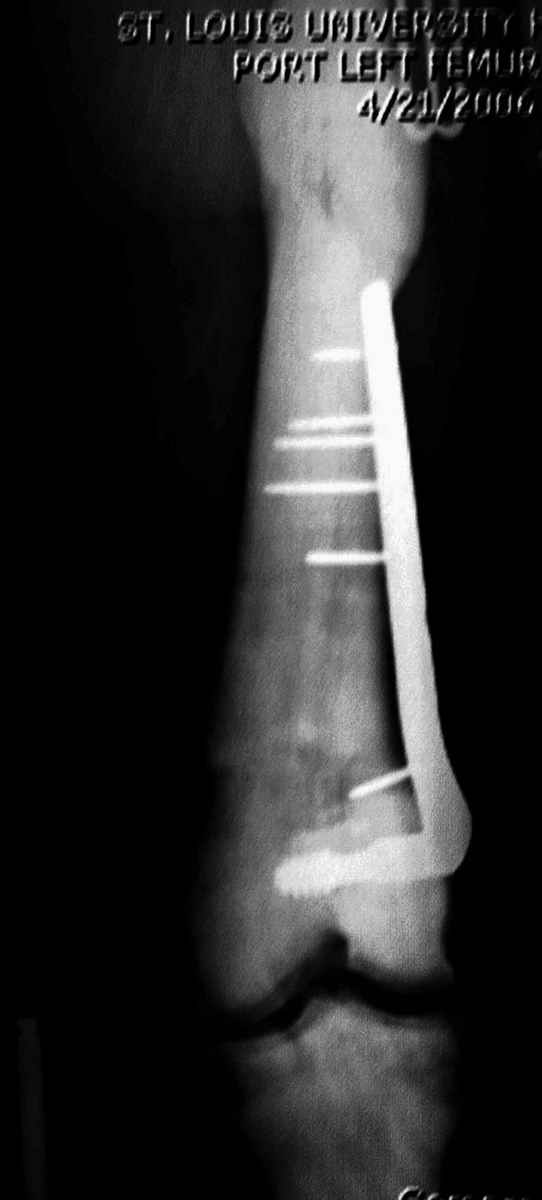

Не являюсь специалистом по костной патологии, но мне кажется, на ренгенограмме множественные мета-диафизарные образования напоминяющее змееподобных извилистых линии и периостеальные ламинирование очень напоминяет картину остеонекроза (инфаркта) костей, возможно связано с длительным применением стероидов.

При предоставлении дополнительных информации, сканнирования, МРТ и лабараторных данных можно уточнить предварительный диагноз, пока склонен к обширному костному инфаркту, и таких больных рекомендуем лечить сиптоматически.

слайды из прошлегодного случая.